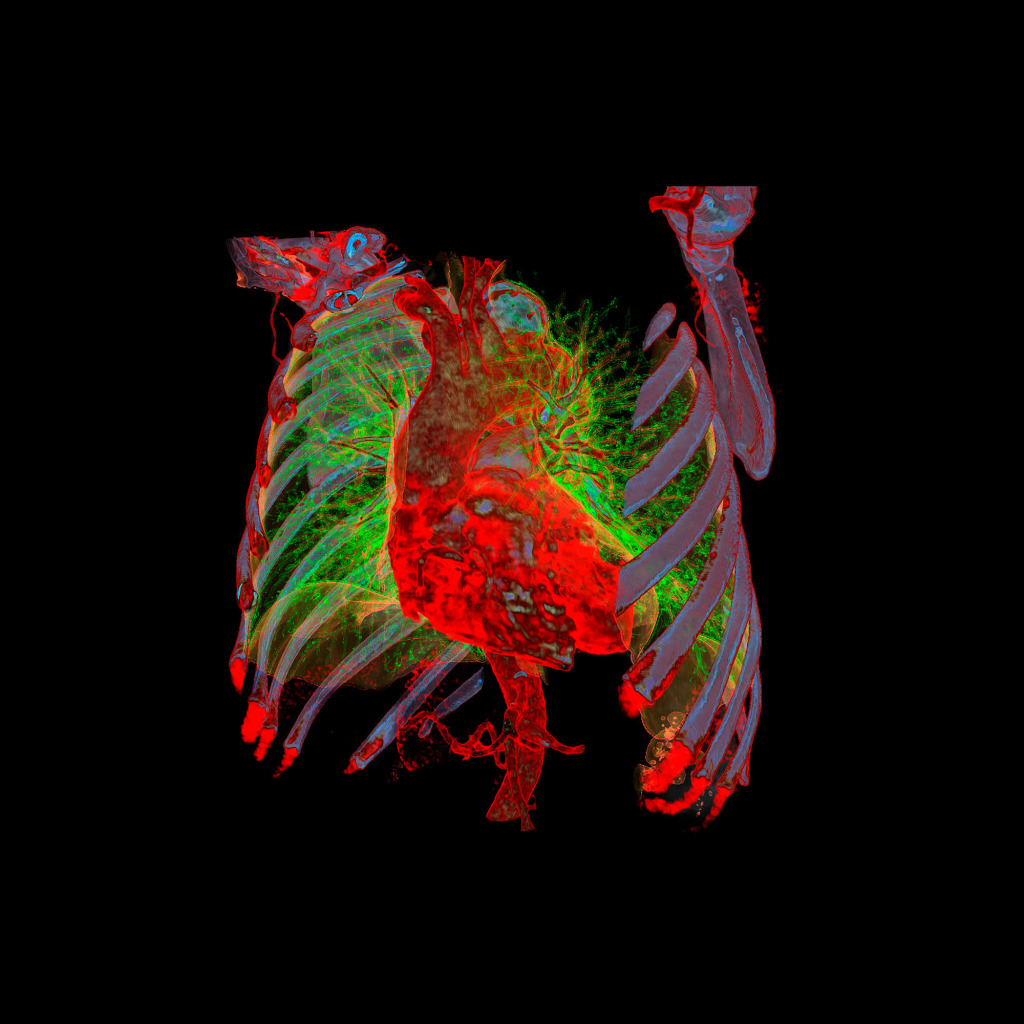

At a lecture on radiology I saw a simple 3D visualisation of a CT examination for the first time. It made an impression on me and the same day at home I started looking for information and software for independent processing of DICOM images. After a few hours, I managed to get a three-dimensional image.

The program for processing radiological images (DICOM archives) allows you to create and look at a three-dimensional image from different angles.

If you change the location of the virtual lens, thereby changing the perspective, you can get such images.

No. Tissues with different densities are best suited to visualisation by CT imaging.

Lungs and heart, bones and muscles or organs injected with a contrast agent reveal the best structure and anatomy.